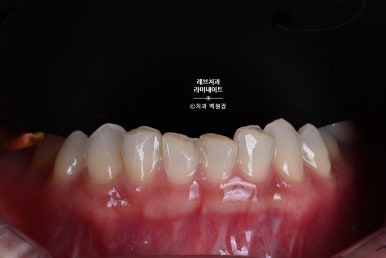

잇몸성형을 하면서, 치아를 다듬어주었습니다.

아래 앞니 레브네이트 베이직을 제작하기 위해 삭제된 치아의 모습입니다.

그렇게 해서 만들어온 레브네이트 베이직을 붙여드렸습니다.

치아가 조금 짧네? 라고 생각할 수 있습니다만, 위 치아의 모양과 환자의 외모를 고려한 치아 형태입니다.

더 길게했다면, 다른 치아들과 분위기가 잘 어울리지 않았을거에요.

약간의 잇몸성형을 통해 아랫니가 조금 더 보이게 함으로써 자연스러움을 추가하였습니다.

아래 앞니의 경우 신경치료 추가 없이, 치아가 시리지 않는 선에서 최소 삭제로 치료해드렸습니다.